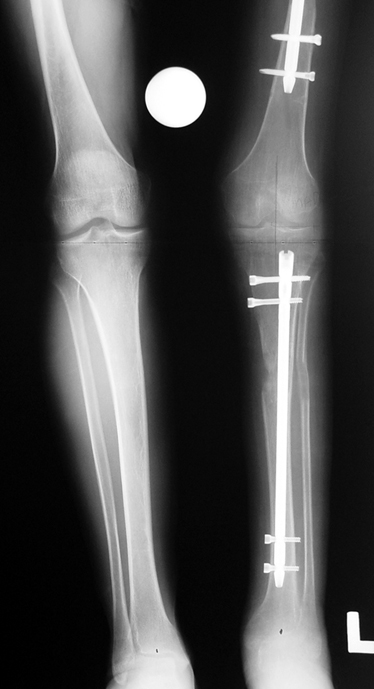

3. POSTTRAUMATIC LOWER LIMB SHORTNESS (MALUNION)

This type of shortness occurs after a fracture heals in a shortened position. Most cases are seen in adults and can be treated with one lengthening operation. Additional deformities can be corrected simultaneously. Most of these cases can be treated with lengthening over nail or just corrections and intramedullary nailing.